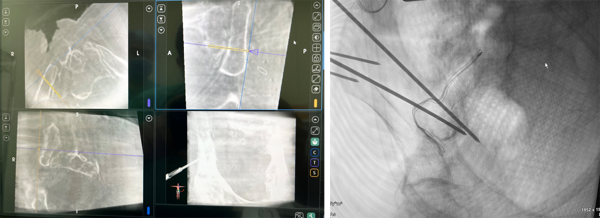

术中王树锋主任医师(左一)与李文军主任医师(右一)在骨科机器人的辅助下精准地置入导针。

术中导航辅助准确定位形态不规则的坐骨大孔,机器人辅助精准置入导针。